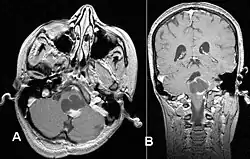

Pilozytische Astrozytome können im Bereich von Großhirn, Zwischenhirn, der hinteren Schädelgrube, des Rückenmarks und auch im Verlauf von Sehnerv (Nervus opticus) und Sehbahn (Tractus opticus) auftreten,[1] wobei in letzterer Lokalisation auch von Optikusgliomen gesprochen wird. Beidseitige Optikusgliome gelten als charakteristisch für die Neurofibromatose Typ 1.

Bei Lokalisation des Tumors im Bereich der hinteren Schädelgrube stehen häufig Störungen der Kleinhirnfunktion wie Gangunsicherheit (Ataxie) im Vordergrund, Tumoren im Bereich des Zwischenhirns machen sich unter anderem mit hypothalamischen Funktionsstörungen bemerkbar. Sind Sehnerv oder Sehbahn betroffen, können Sehstörungen bis hin zur Erblindung auftreten.